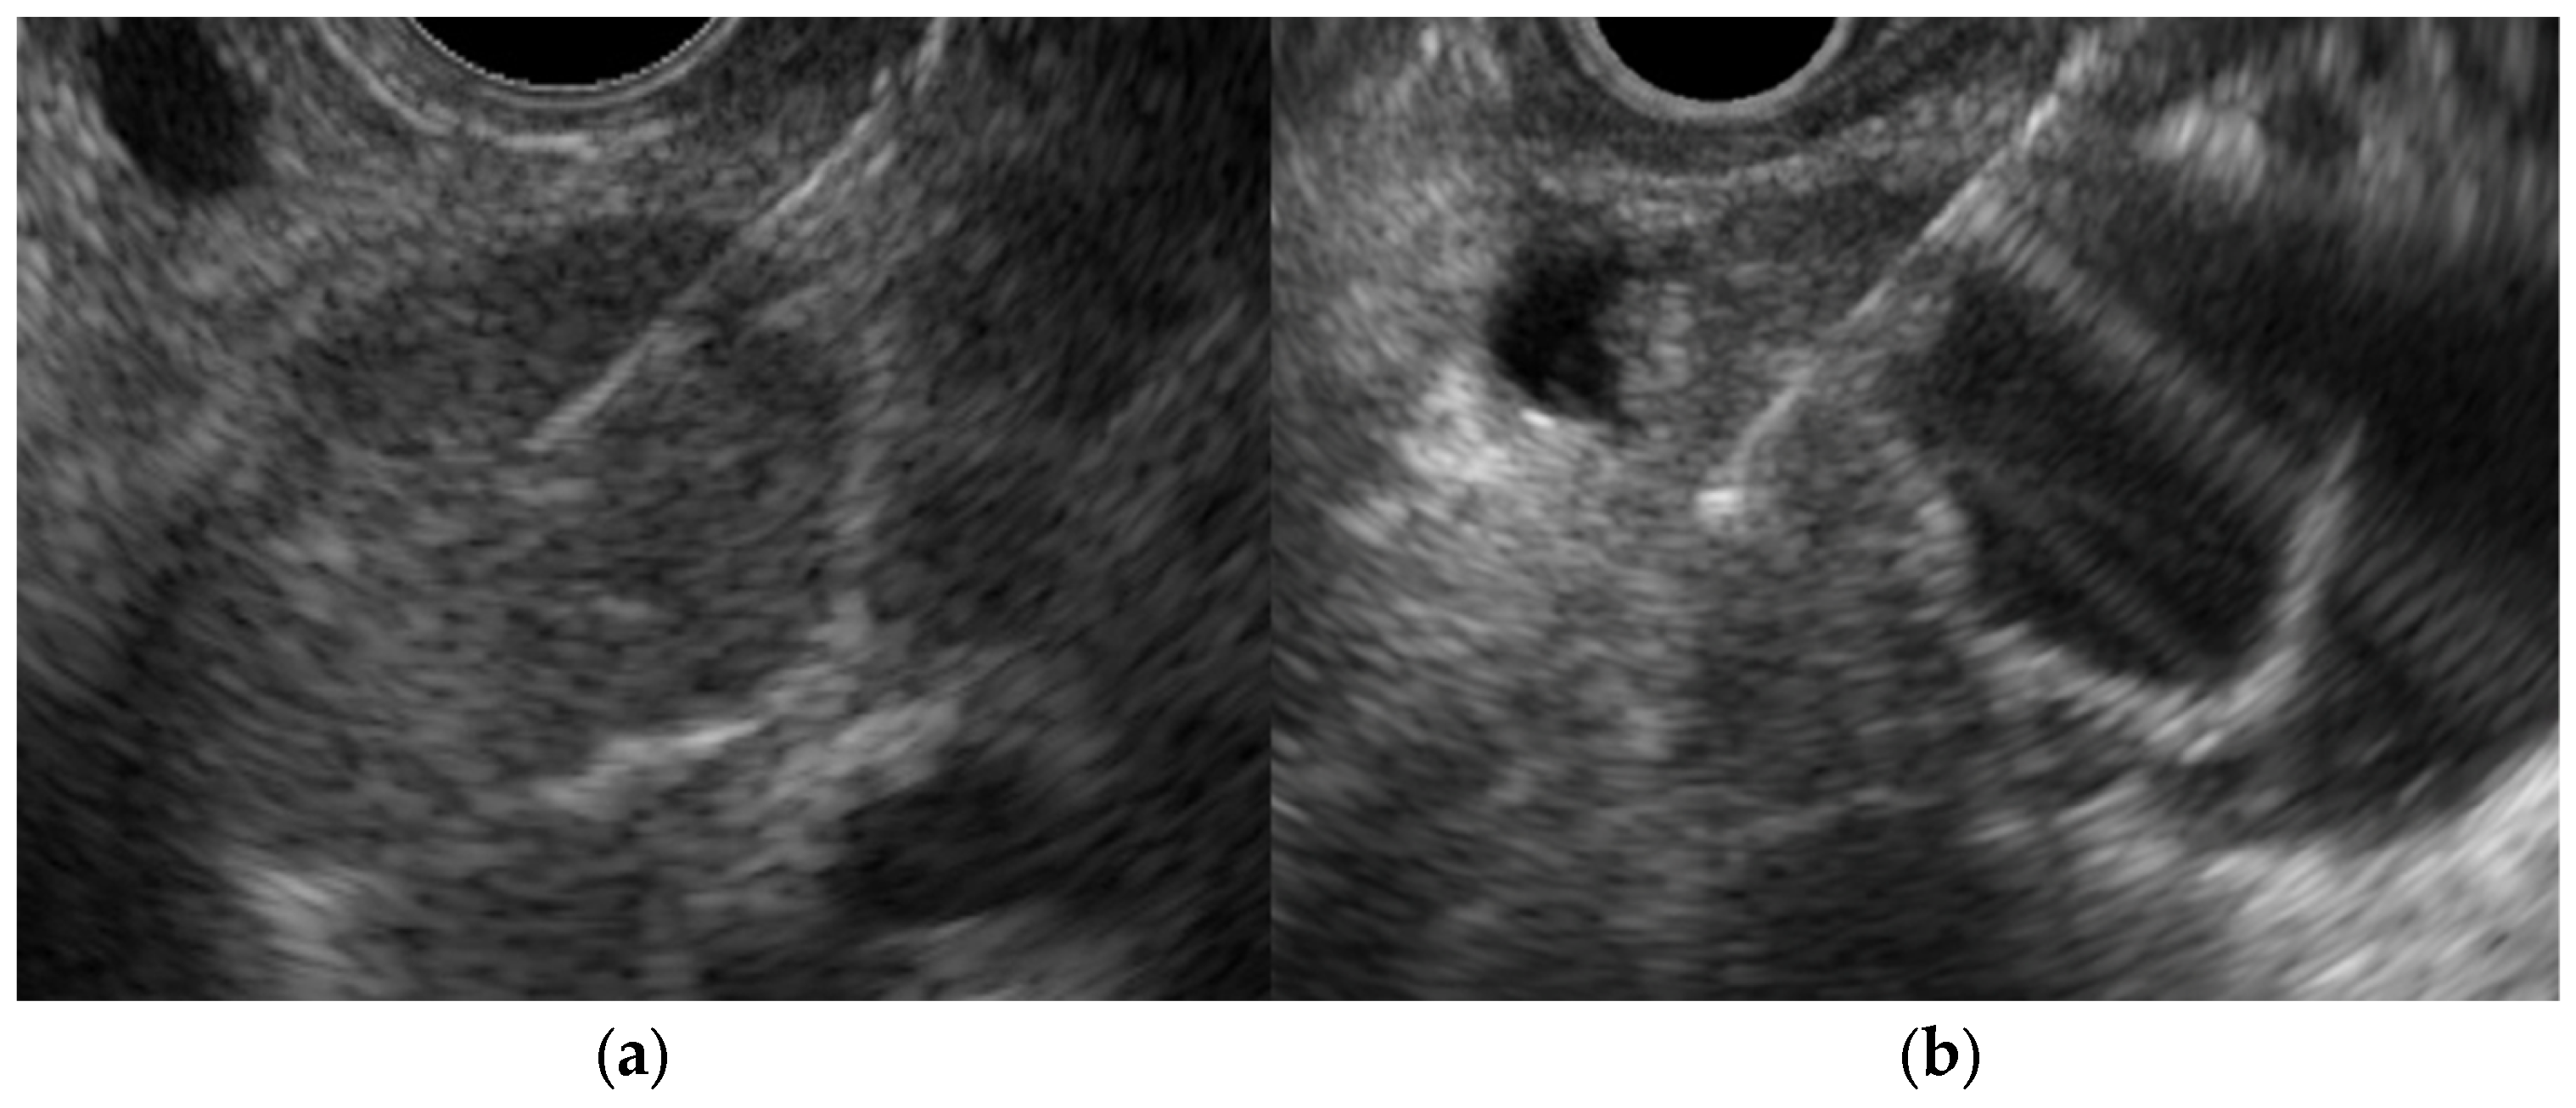

- Immunoglobulin G4-related sclerosing cholecystitis (IgG4-CC) (Figure 3)

| Immunoglobulin G4-related sclerosing cholecystitis | Smooth | No distinctive findings | Preserved |